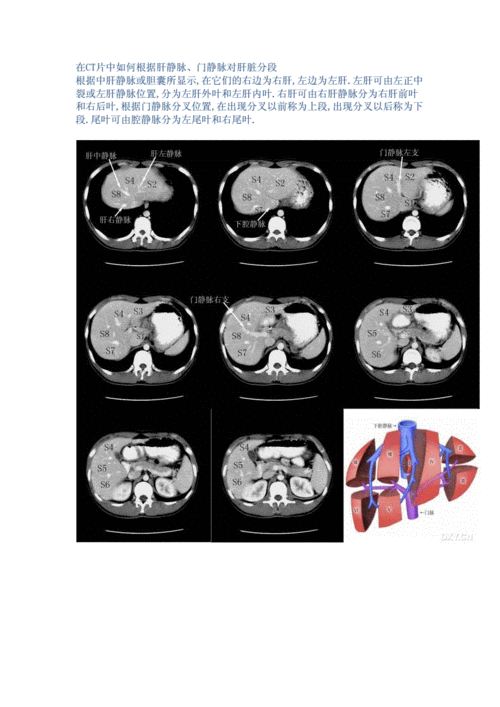

ct肝脏分段解析

肝脏ct分段

肝脏分叶分段ct图像

肝脏ct分叶分段解剖图

肝脏ct分段解剖图

肝脏分段ct断面解剖图

肝叶分段ct示意图

ct肝脏分段图

肝脏分段ct

肝脏分段8段CT